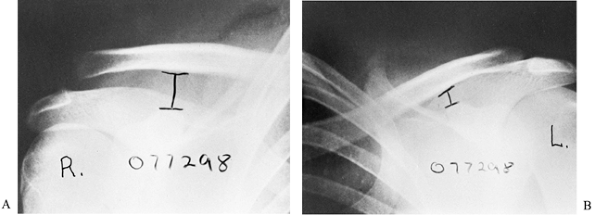

standing or sitting, with the back against the x-ray cassette and the

arms hanging unsupported at the side, imaging both shoulders

simultaneously on one large (14 × 17-in.) cassette.

shoulders, including the lateral third of the clavicle if possible.

This view will reveal any posterior displacement of the clavicle as

well as any small fractures that may have been missed on the

anteroposterior view.

anteroposterior radiograph with 10- to 15-lb weights suspended from

each arm with wrist straps. The weights should be hanging from the

wrists rather than held by the patient to encourage complete muscle

relaxation (Fig. 78.5).

normal, except for mild soft-tissue swelling, as compared with the

uninjured shoulder. There is no widening, no separation, and no

deformity. In a type II injury, the lateral end of the clavicle may be

slightly elevated, and the AC joint may appear to be widened. Stress

films reveal that the CC space is the same as that of the normal

shoulder.

with the lateral end of the clavicle displaced completely above the

superior border of the acromion. The CC interspace is significantly

greater than that in the normal shoulder (Fig. 78.8).

| Figure 78.8. Radiograph appearance of a grade III injury to the right shoulder. Stress radiograph films were made to compare the right shoulder with the left. Not only is the right AC joint displaced compared with the left, but, more significantly, notice the great increase in CC interspace on the injured right shoulder compared with the normal left shoulder. |